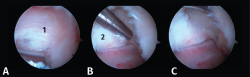

- Tercer paso. El sinoviotomo se gira ahora para que la ventana vuelva a mirar la cara medial del PPA. En este momento, el tendón FHL permanece medial al sinoviotomo y opuesto a su ventana. Podemos así seccionar el retináculo del FHL con el sinoviotomo o mediante una pinza de tipo basket (Figuras 6 A, B y C).

Figura 6. A y B: liberación del retináculo del flexor hallucis longus (FHL) (1); C: evaluación del interior de la vaina del FHL (2).

Evaluación del tendón flexor hallucis longus

El tendón del FHL se valora sistemáticamente mediante el gancho explorador, pudiendo encontrar tenosinovitis y/o atrapamiento por la presencia de una unión musculotendinosa de implantación baja. A continuación, se introduce el artroscopio en la propia vaina para poder evaluar el resto del recorrido del tendón (Figura 6 C).